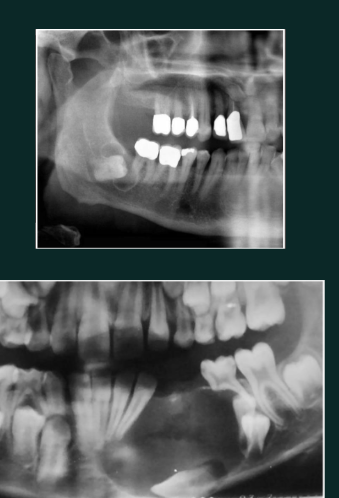

Condensing osteitis

RO lesion

RO at apex

linked with non vital tooth

no RL halo

Odontoma

RO

Compound

tooth like structure; denticles

anterior maxilla

Complex

RO mass with no tooth structures

posterior mandible

Cementoblastoma

RO mass fused to root

surrounded by RL halo

may cause expansion

may cause displacement, resorption can occur

tooth remains vital

pain may be present, but not always